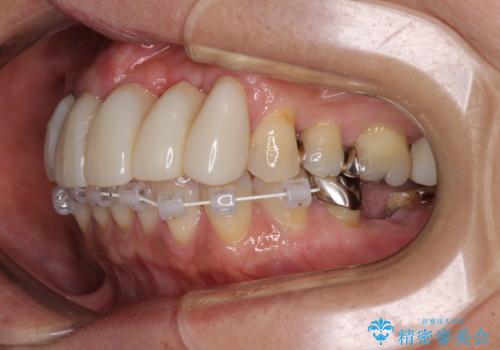

- 前歯の歯肉の腫れを気にして来院された患者様です。

前歯のみならず、奥歯の銀歯や下顎前歯のデコボコなど、色々と気になる部分を治したいとのことでした。

前歯は抜歯が必要であったので、抜歯を行い、その後歯肉移植をおこなった上でオールセラミックブリッジによる補綴治療を行うこととしました。

下顎と上顎臼歯部については矯正治療を行い、奥歯の欠損部位はオールセラミックブリッジを、その他の銀歯はセラミックインレーなどにより治療を行うこととしました。